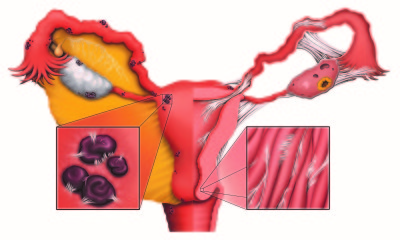

Порушення можуть бути зумовлені різними факторами та найсерйознішими з них є патологічні стани. Патологія яєчників впливає не тільки на рясність виділень, але і їх частоту. У цей процес можуть бути включені ушкодження різного типу та злоякісні новоутворення.

Якщо йдуть місячні дуже рясно і за один цикл це відбувається більше одного разу, не виключена ймовірність розвитку поліпів. Хронічний запальний процес може призвести до пошкоджень в порожнині матки, що і провокує часті виділення.

Нерідко постійні менструації не пов'язані з роботою яєчників і всієї сечостатевої системи жінка. На цей процес здатні вплинути аборти або вискоблювання порожнини матки. Під час усунення ембріона можуть бути зроблені механічні пошкодження, в результаті чого протягом тривалого часу фіксуються виділення. Якщо вони рясні, це вказує на серйозне пошкодження або втягнення в процес запалення.Кровоточити може прооперований яєчник. В результаті хірургічного втручання розвивається дисфункція системи. Це призводить до нерегулярних менструацій.